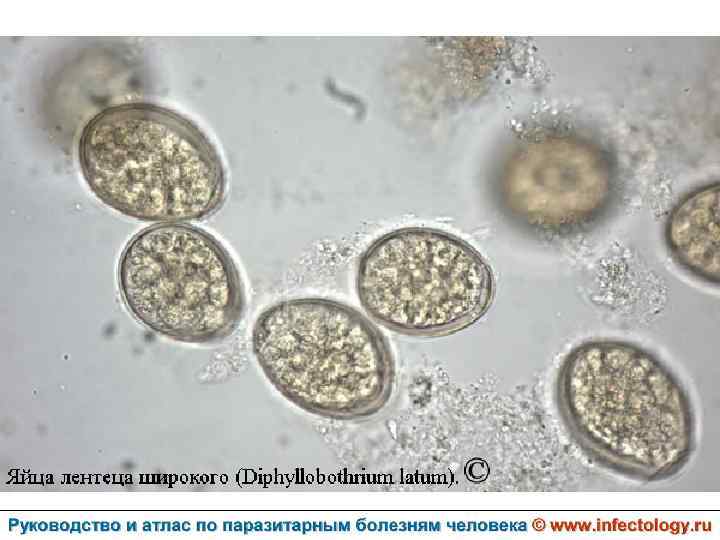

Дифиллоботриоз (шифр по МКБ 10 – B 70. 0) – зоонозный биогельминтоз с хроническим течением, характеризующийся нарушением функций верхнего отдела пищеварительного тракта, а при тяжелом течении - развитием анемии.